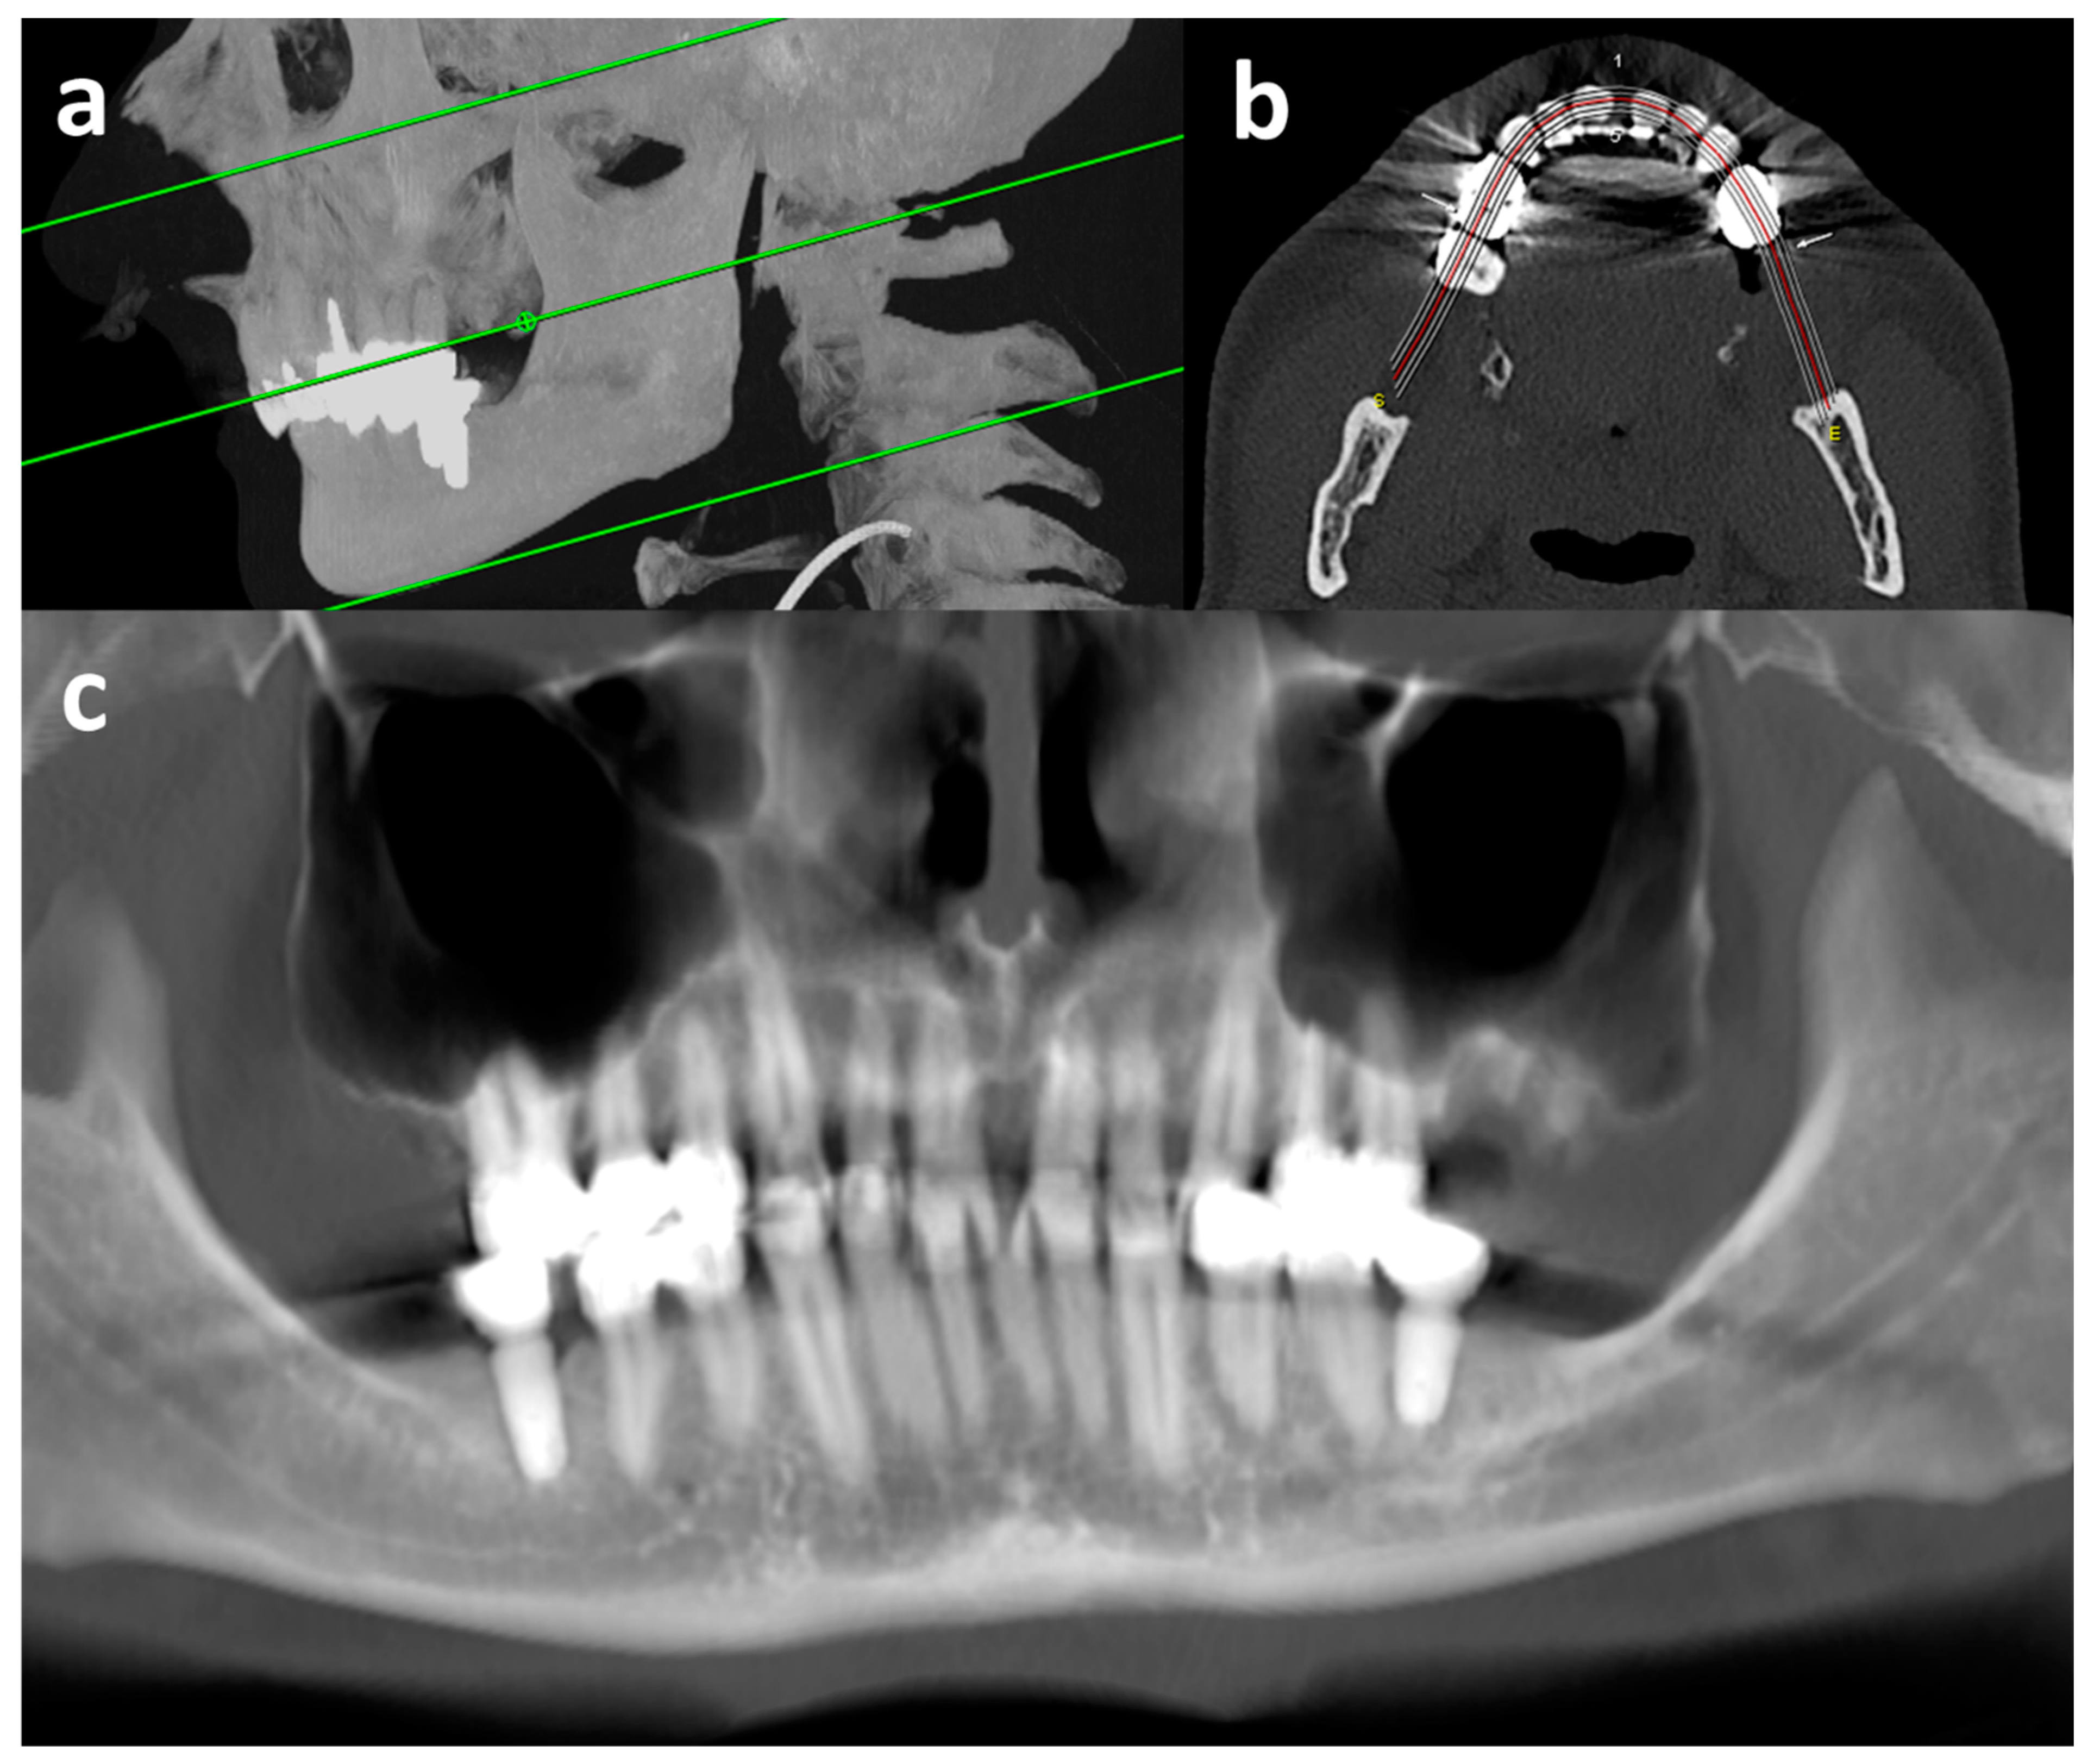

2.2. Image Acquisition, Reconstruction, and Radiographic Assessment

2.2.1. CT

2.2.2. Virtual Orthopantomogram (vOPG)

2.2.3. Radiological Evaluation